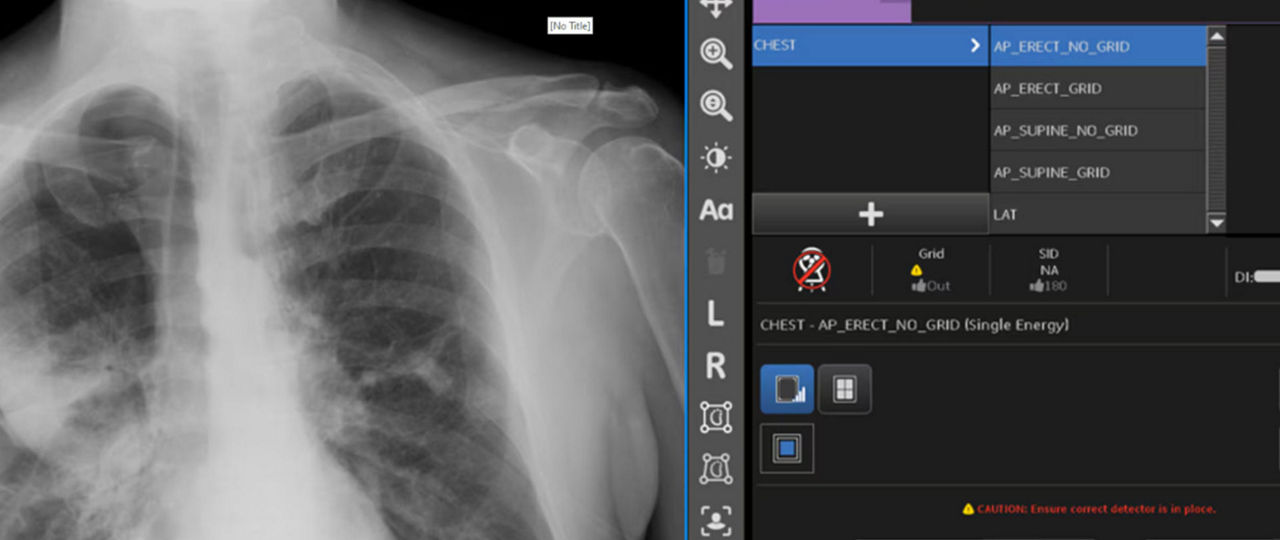

INTELLIGENT AUTO ROTATE

Intelligent Auto Rotate automatically detects if an image is not upright and rotates the image to be upright for the viewer. This feature saves technologists approximately 3-4 user interface clicks on 85% of mobile X-ray exams, saving ~ 187,000 clicks a year.1